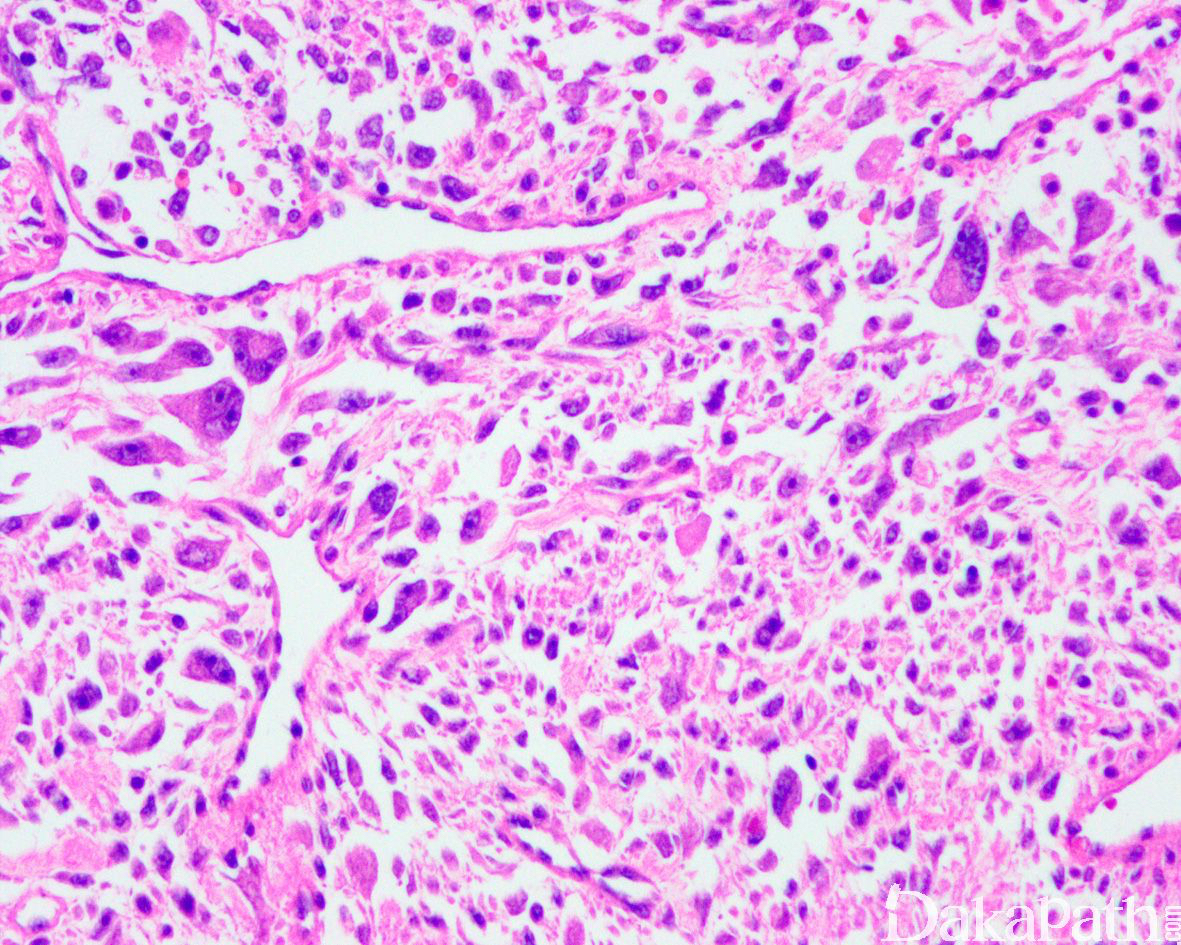

如前所述,DDLPS 组织学上通常表现为 ALT/WDLPS 成分向非脂肪源性的肿瘤成分转化,2 种成分在镜下通常分界较清楚,表现为突然的过渡;但有时可表现为逐渐的过渡或在整个肿瘤内交错的分布(马赛克样的去分化),这一情况尤其在伴有低级别去分化时常见。肿瘤可能部分带假包膜或边界清楚,但至少局部可见推挤状或浸润性边界,后腹膜的 DDLPS 常见累及周围实质器官(如肾脏等)。高分化与去分化成分的比例在不同肿瘤内多少不等,有时候即使在广泛取材的情况下高分化成分也可能完全确如,而去分化成分通常较广泛,但有时也可能仅仅不足 1 cm(又称为微小去分化)。DDLPS 中的 ALT/WDLPS 组织学类型以脂肪瘤样和硬化性为主,而去分化成分大多数表现为高级别去分化特征包括高级别多形性肉瘤样(多形性瘤细胞伴有席纹状排列类似于多形性未分化肉瘤/恶性纤维组织细胞瘤)、高级别梭形细胞肉瘤样(细胞密度较高的梭形瘤细胞伴有交错束状或鱼骨样排列类似于纤维肉瘤)以及少见的高级别圆细胞肉瘤样(弥漫的小蓝圆细胞类似于骨外尤文肉瘤或差分化的滑膜肉瘤)和上皮样特征(弥漫成片的上皮样瘤细胞伴有丰富的嗜酸性胞质或横纹肌样特征类似于转移性癌或恶性间皮瘤),高级别去分化成分通常瘤细胞密度高,间质稀少,核分裂象活跃(> 5 个/10 HPF),但比较于与之类似的肿瘤而言,去分化成分的核分裂象相对较少;坏死较为常见。